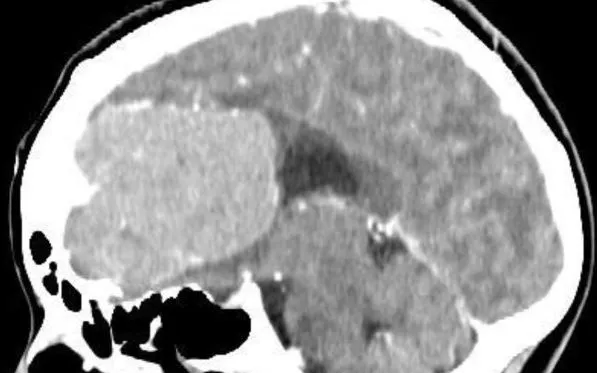

Qua thăm khám và chụp cộng hưởng từ (MRI) sọ não có thuốc cản quang, các bác sĩ phát hiện khối u não kích thước khoảng 65x80mm nằm ở tầng trước nền sọ, gây đè đẩy đường giữa 19mm. Nếu không được xử trí kịp thời, người bệnh có nguy cơ gặp biến chứng thần kinh nặng nề.

ThS.BS Đồng Tiến Phúc, Khoa Phẫu thuật thần kinh - Cột sống cho biết, khối u có kích thước lớn và nằm ở vị trí phức tạp, gần nhiều mạch máu quan trọng như động mạch cảnh trong nên tiềm ẩn nguy cơ chảy máu hoặc đột quỵ trong quá trình phẫu thuật.

Sau hơn 2 giờ phẫu thuật, ekip đã bóc tách thành công toàn bộ khối u. Sau mổ, bệnh nhân được hồi sức và theo dõi sát sao. Việc loại bỏ khối u kịp thời giúp giảm áp lực nội sọ và hạn chế nguy cơ thiếu máu não do khối u chèn ép mạch máu lớn.